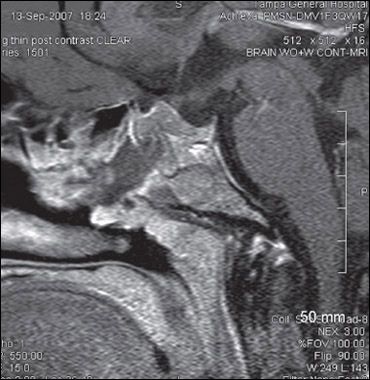

The patient underwent resection of a macroadenoma; however, only part of the tumor could be removed (Figure 3). Because preoperative laboratory results suggested central adrenal insufficiency, she received a stress dose of corticosteroids intraoperatively, which was reduced to a maintenance dosage after surgery. The postoperative course was complicated by rhinorrhea and partial central diabetes insipidus. Oral desmopressin (0.1 mg bid) was initially required to maintain her euvolemic status; this was slowly decreased over 2 months. Long-acting formulations of octreotide and cabergoline were also started and then titrated to maximally recommended doses.

Figure 3 – An MRI scan after partial resection of the macroadenoma shows residual tumor.

Surgical management. Surgical removal or debulking of the tumor remains the primary mode of therapy. Even for patients without compressive symptoms, surgery followed by medical therapy allows for better normalization of IGF-1 and GH levels. In some instances, such as when the presence of large bulky infiltrating tumors prohibits surgery or when the patient is not a good surgical candidate, medical management may be the primary treatment modality.

Prognostic factors in favor of a good outcome after surgery include smaller size of the tumor, basal GH levels of less than 45 ng/mL, and an experienced surgeon (a surgeon who has performed more than 100 pituitary surgeries or has more than 20 pituitary cases per year). Cure rates are about 70% for microadenomas and less than 50% for macroadenomas.1